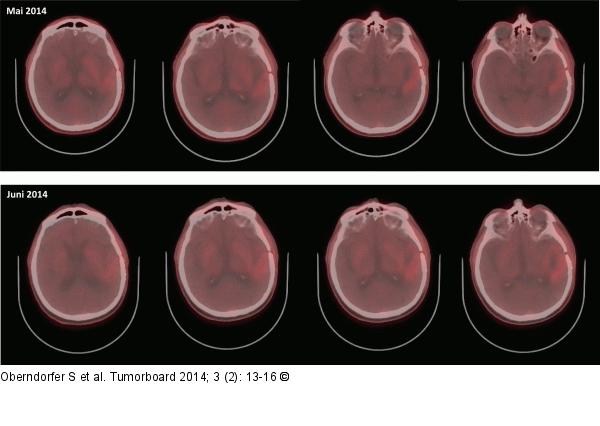

Abbildung 5: Glioblastom Follow-up-Imaging vom Juni 2014: im FET-PET trotz rezidivierender fokal komplexer Anfälle kein vermehrter Tracer-Uptake im Vergleich zu den Vorbildern vom Mai 2014 |

Follow-up-Imaging vom Juni 2014: im FET-PET trotz rezidivierender fokal komplexer Anfälle kein vermehrter Tracer-Uptake im Vergleich zu den Vorbildern vom Mai 2014 |